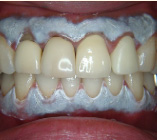

セラミック治療

こんな歯並びでもご心配なく。矯正という方法をとらなくても、ここまできれいに治せるんです。見た目だけでなく歯ブラシもやり易くなりました。笑顔に自信がつきますよ。

- 施術前

- 施術後